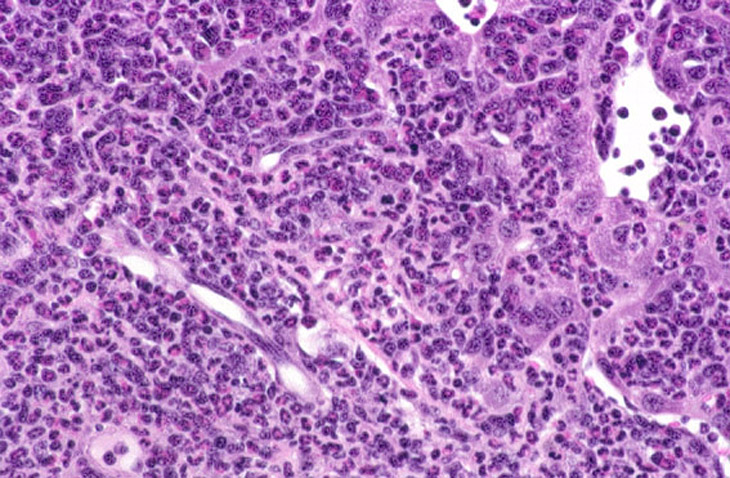

A spectrum of lesions affecting the liver and other tissues has been observed in Tg.AC mice treated with rotenone. The lesions appear to represent a morphological and biological continuum with varying features of hematopoietic, inflammatory, and neoplastic processes. The cellular infiltrates consist of a mixture of immature and mature myeloid cells and mononuclear cells including plasma cells, often with a striking eosinophil component. The granulocytic infiltrates are often immature and megakarocytes as well as erythropoietic foci may be present. Hyaline degeneration and proliferation of bile ducts has been noted in some cases.

Another case of myelodysplasia. Numerous granulocytes with eosinophilic granular cytoplasm and a smaller number of mononuclear cells are visible in the high magnification view.